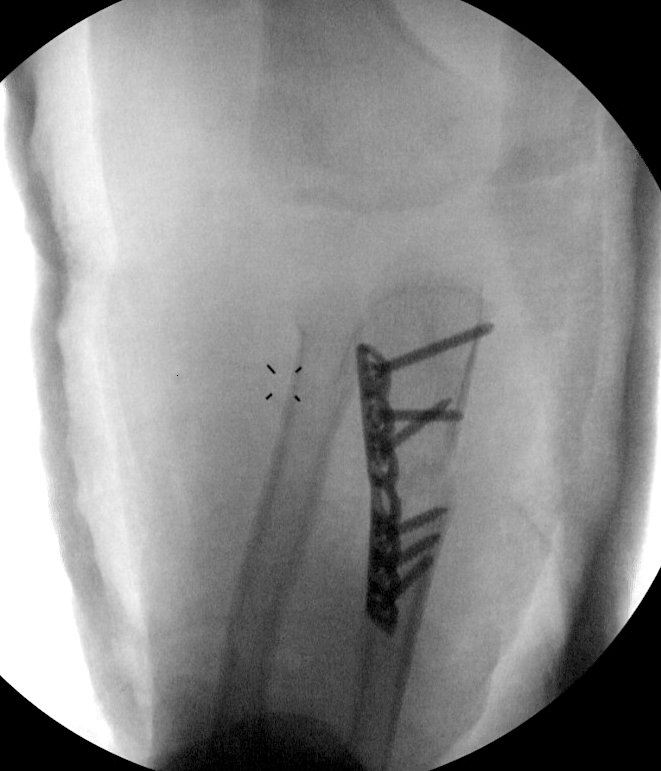

A. Ensure ulna fracture out to length / stabilise with K wire / IM nail / plate

B. Plastic deformity of ulna may need to perform osteotomy to reduce radial head

C. May require open approach to radial head with relocation

D. Radial head remains unstable - repair annular ligament or stabilise with strip of triceps fascia

- open reduction radial head

- opening wedge osteotomy of the ulna

- annular ligament repair +/- reconstruction with strip of triceps fascia